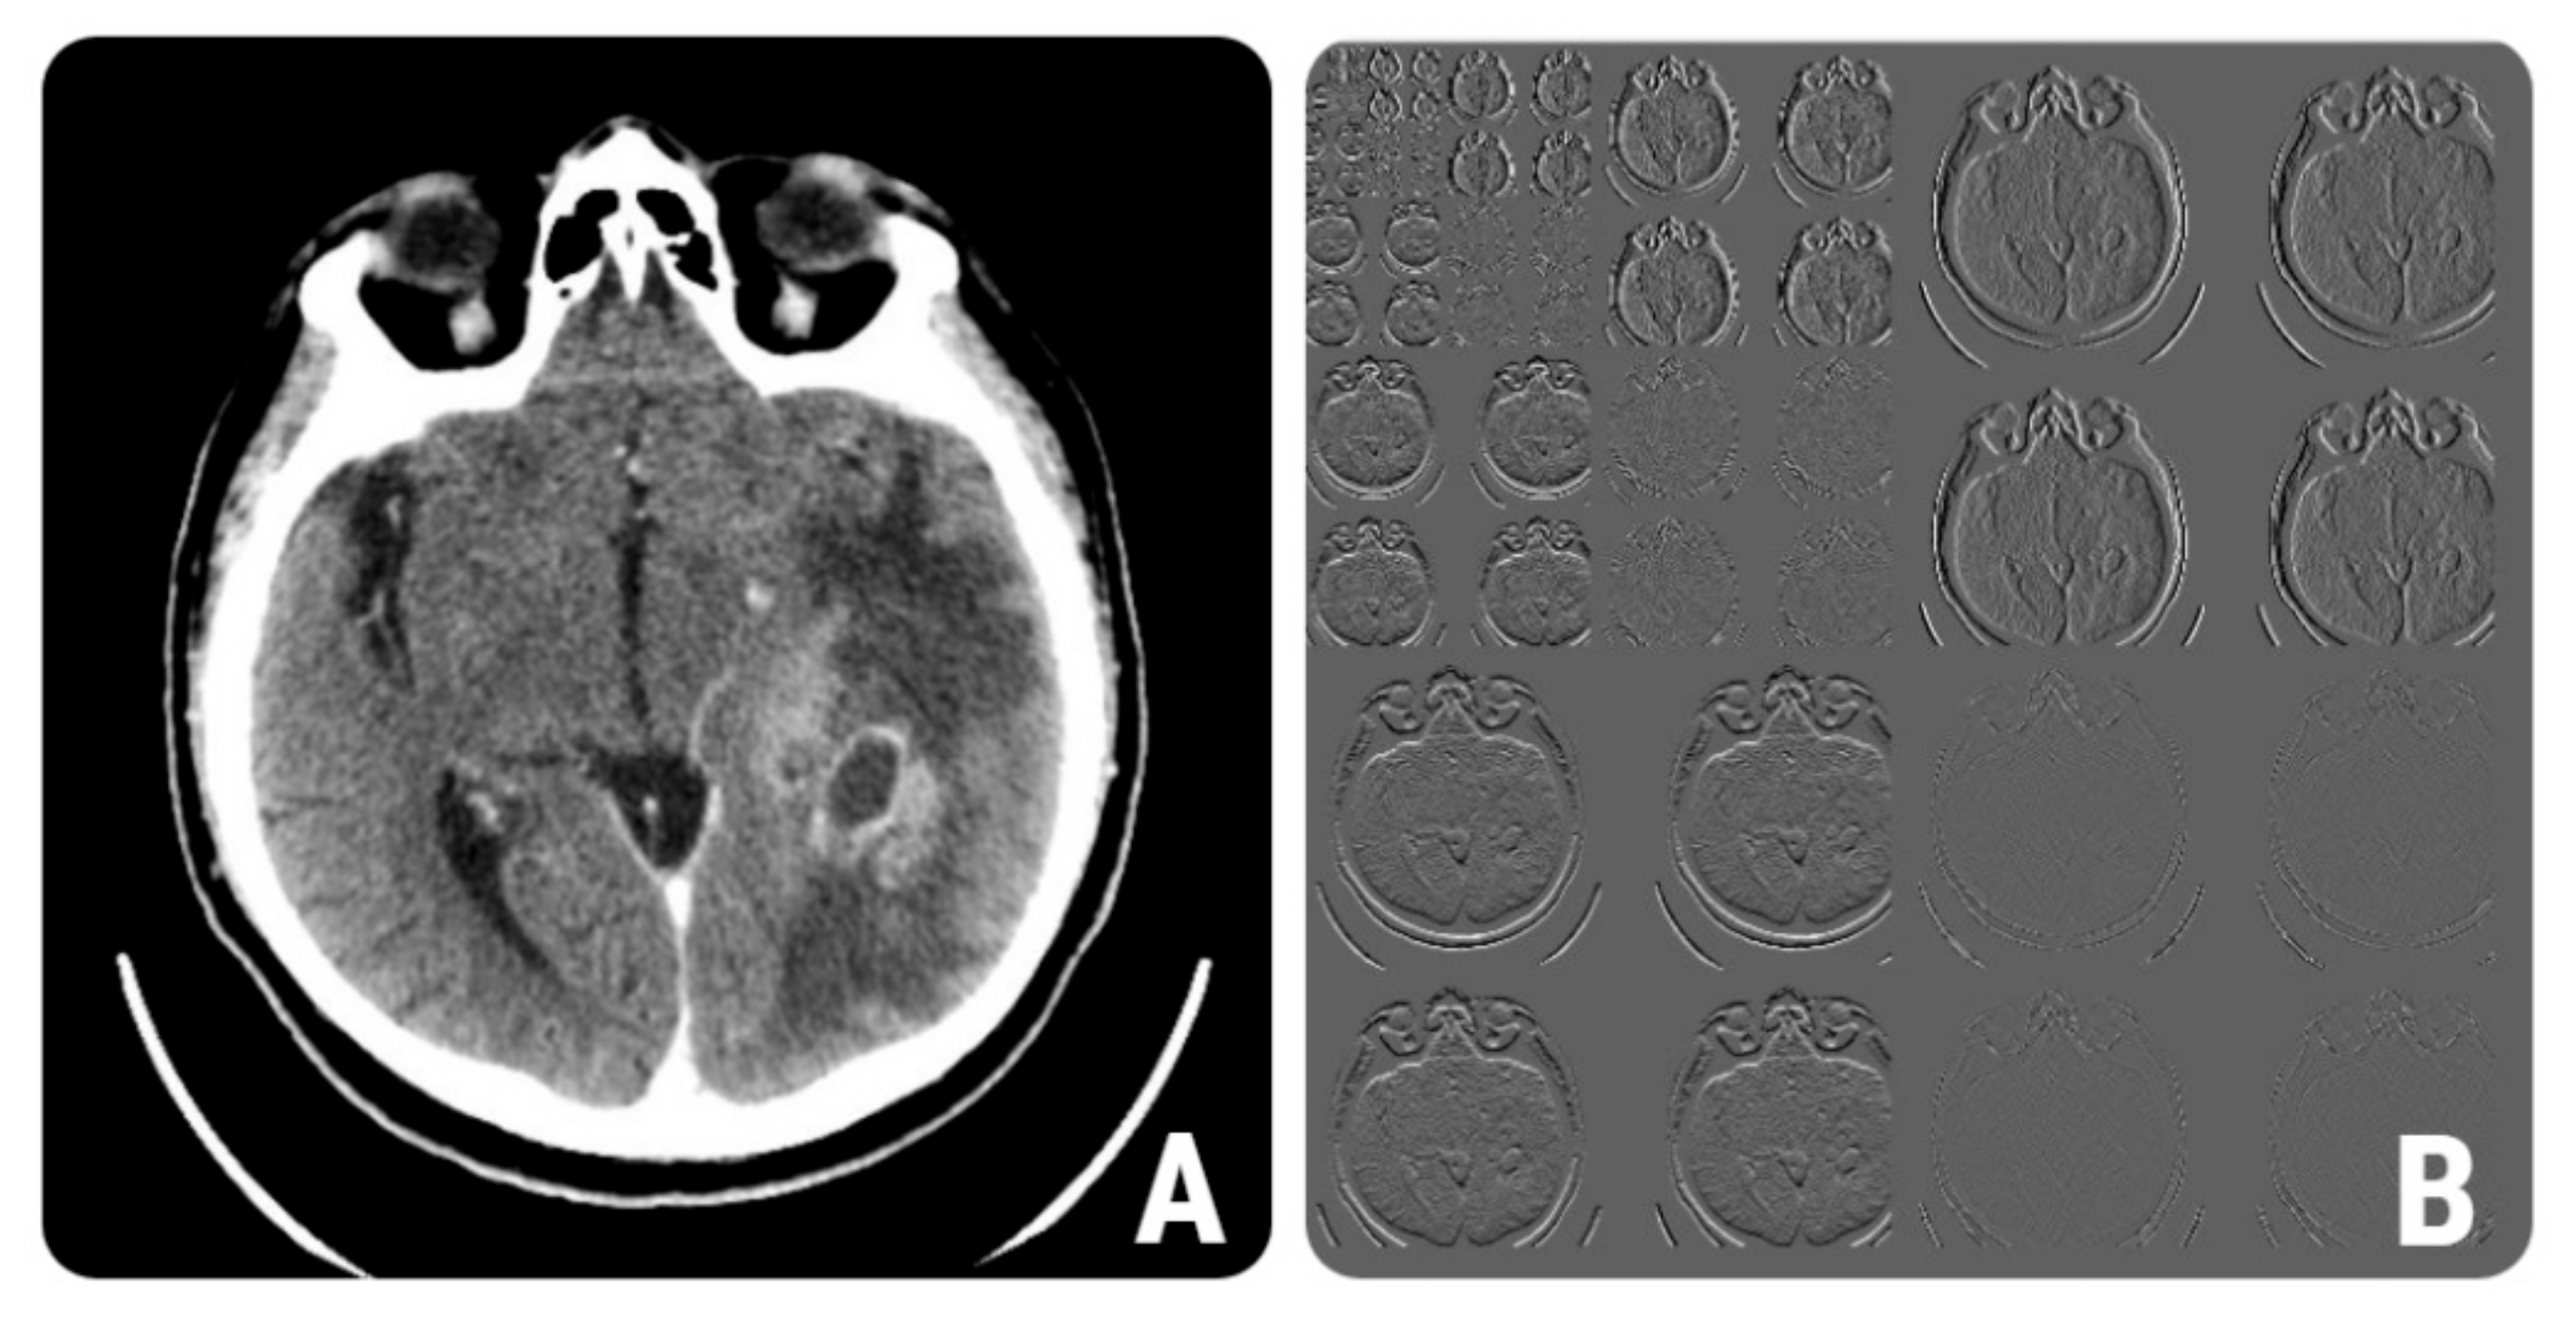

Wavelet transformation is a multiresolution technique that aims to transform images into a representation that contains both spatial and frequency information [21]. Wavelet energy quantifies the distribution of energy along the frequency axis over scale and orientation. Energy measures the local uniformity within an image [22]. We obtained higher values for BMs of both wavelet energy parameters (WavEnHH_s-2 and WavEnHL_s-3) that were selected by the reduction techniques. An example of the wavelet multi-level decomposition of a CT image of a patient with glioblastoma is displayed in Figure 5.

Figure 5.

(A) Contrast-enhanced CT image of a 57-year-old patient with histologically proven grade IV glioblastoma. (B) The wavelet multi-step decomposition of image (A).